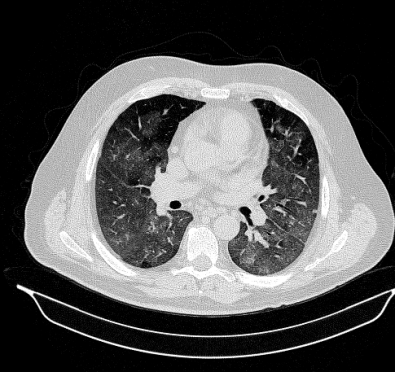

Lung segmentation results for the polymorphic and nonpolymorphic models are shown in Figure 3. Quantitative evaluation of lung segmentations was performed on CT images by comparing the segmentations to ground truth manual segmentations. The Dice coefficient was used to measure volume overlap and the average symmetric surface distance (ASSD) was used to assess boundary accuracy. The ASSD and Dice coefficient results for each of the four evaluation datasets are shown in Table 2. Overall, on the COVID-19 dataset the polymorphic model achieved an average ASSD of mm and average Dice coefficient of . By comparison, the nonpolymorphic model achieved an average ASSD of mm and average Dice coefficient of . ASSD and Dice coefficient results with respect to nonaerated lung volume fraction are displayed in Figure 4. Two-way analysis of variance revealed a significant interaction between model and nonaerated fraction for each evaluation metric, indicating that the regression coefficients with respect to nonaerated fraction were significantly different for polymorphic vs. nonpolymorphic models.